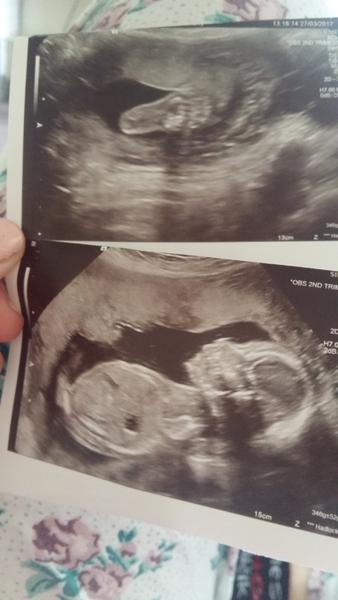

Taak je zdravá, Dr jej pozerala vnútorné orgány atď..Všetko vraj vyzerá dobre 🙂 dĺžku mi nepovedala,ale odmerala stehennu kosť 🙂 Keďže sme jej povedali že sme boli na privátne Sono pohlavia; tak to len pozrela a povedala že to vyzerá na dievčatko,ale keby to je chlapček; myslím,že vajíčka by bolo už dostatočne dosť vidieť 😃

Malinka pekne kopka, a včera v brusku lezala na boku a mala hlavičku položenú rúčkou, presne ako jej ocinko 😂😂😘😘😘

Prikladám fotku nožičky;ale kedže sa pohla tak je to dosť rozmaznane,ale mne to nevadí 🙂

Moje bruško..Dnes som podla sona 19+5tt

@cvikla12 Ďakujem moja 😘😍 aj riadna bacula asi bude 😂😂😂 vraj 346g +/- 52 g 😃😃🙈🙈🙈🙈

@patkaamirko Babika je super na fotecke 😉...Ta prva fotecka su nozky roztiahnute, dobre som to pochoplia, ci?...Ty si nadherna medzi narciskami a brusenko mas krasnucke - pekna fotecka do albumu tehulkovskeho 😍...Som rada, ze ste obe uplne v pohode a ze pekne rastiete...Daj mi vediet o tej prvej fotke, ci ju dobre chapem 😉